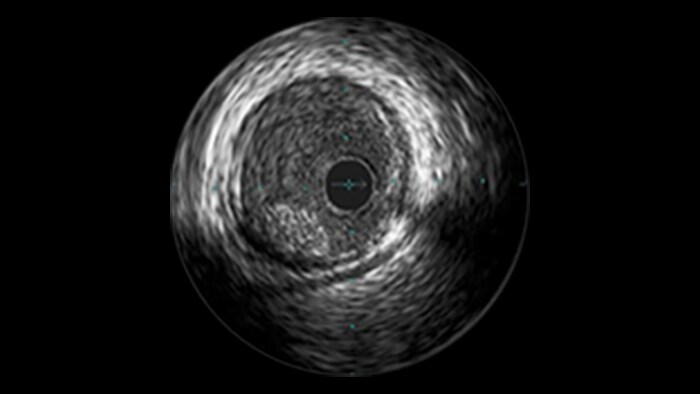

Calcified Lesions

Clinical challenges

Advanced tools for optimal PCI outcomes